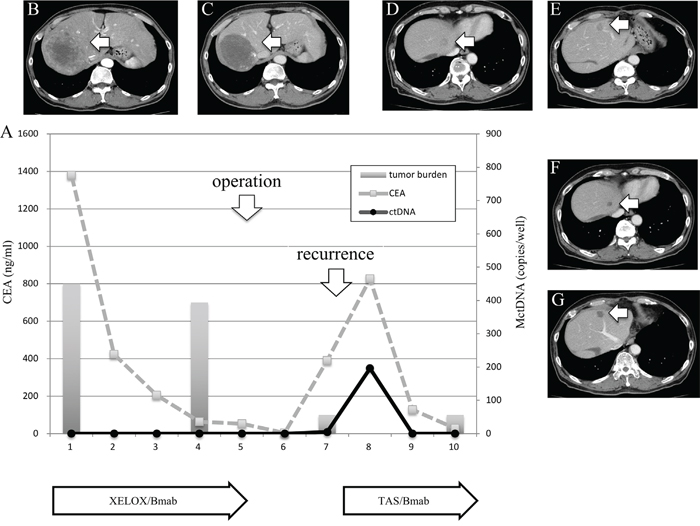

Clinical course of two patients who showed a spike in elevation in mutated circulating tumor DNA

Figure 5: Clinical course of a mCRC patient with multiple liver metastases (A) with morphological changes seen with computed tomography (CT) (B–G) and a spike in elevation in MctDNA. A 60-year-old male with multiple liver metastases is denoted as patient 76. He was treated with XELOX + bevacizumab as the first-line treatment. (B) and (C) show CT images before and after treatment with XELOX + bevacizumab. A change in tumor morphology from heterogeneous to homogeneous low-attenuation was seen in the liver metastases four cycles after treatment with XELOX + bevacizumab despite no change in tumor size. The patient found XELOX + bevacizumab treatment difficult because of severe adverse events and he underwent surgery (right lobectomy for the main tumor and partial resection for other multiple metastases). Soon after surgery, a recurrent liver tumor was found along with increased levels of carcinoembryonic antigen (CEA). Chemotherapy was suggested but the patient refused because of the previous severe adverse events with the first-line treatment. TAS-102 + bevacizumab was then suggested because TAS-102 did not show severe adverse events. Soon after treatment with TAS-102 + bevacizumab, CEA drastically decreased and liver tumors showed morphological changes, which were also seen with the first-line treatment. Additionally, a spike in elevation in MctDNA was observed during this drug response.